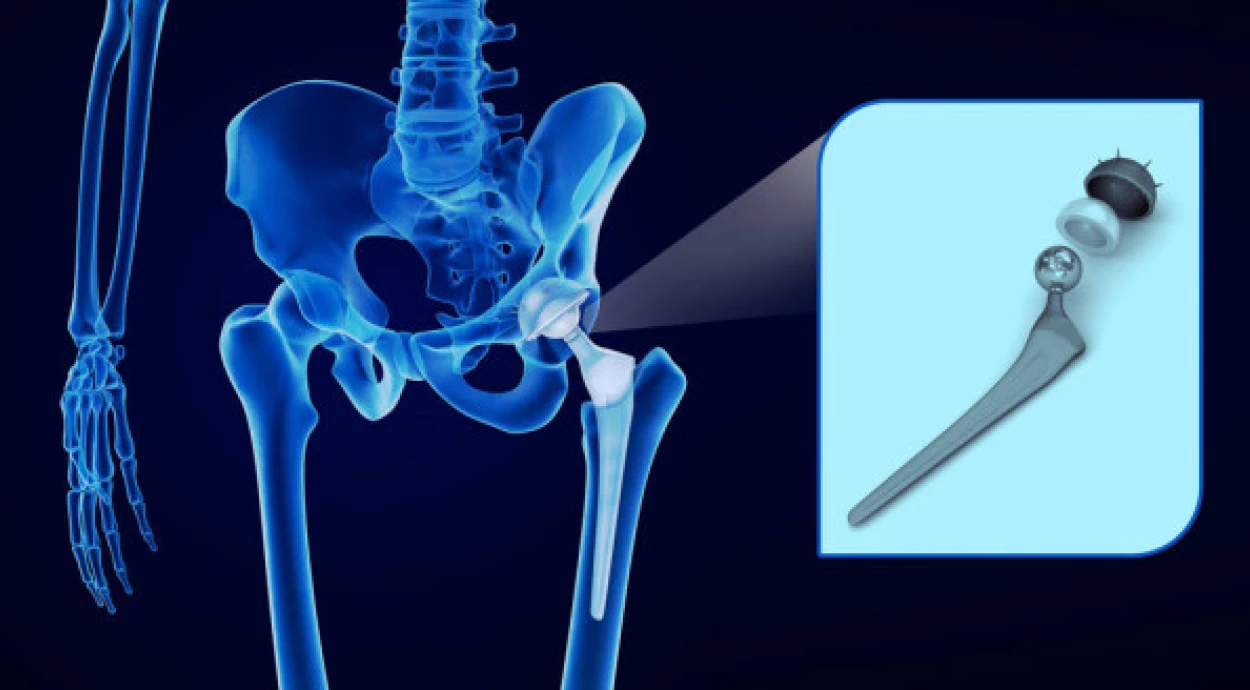

Тотальное и частичное эндопротезирование тазобедренного сустава

При тотальном заменяют головку и шейку бедренной кости, поверхность вертлужной впадины и суставный хрящ, то есть все элементы сустава и тканей, к которым он крепиться.

При частичном эндопротезировании головка бедра сохраняется. Удаляют только остеофиты (костные наросты) и поврежденный хрящ. При необходимости также очищают и вертлужную впадину, после чего устанавливают протез.

установка протеза – хирург делает продольный разрез в области сустава и обеспечивает доступ к нему, удаляет поврежденные ткани и устанавливает протез;